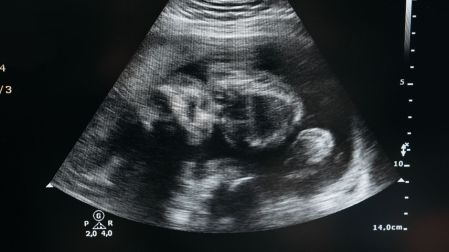

El diagnóstico suele realizarse mediante estudios de imagen como:

- Ultrasonido pélvico